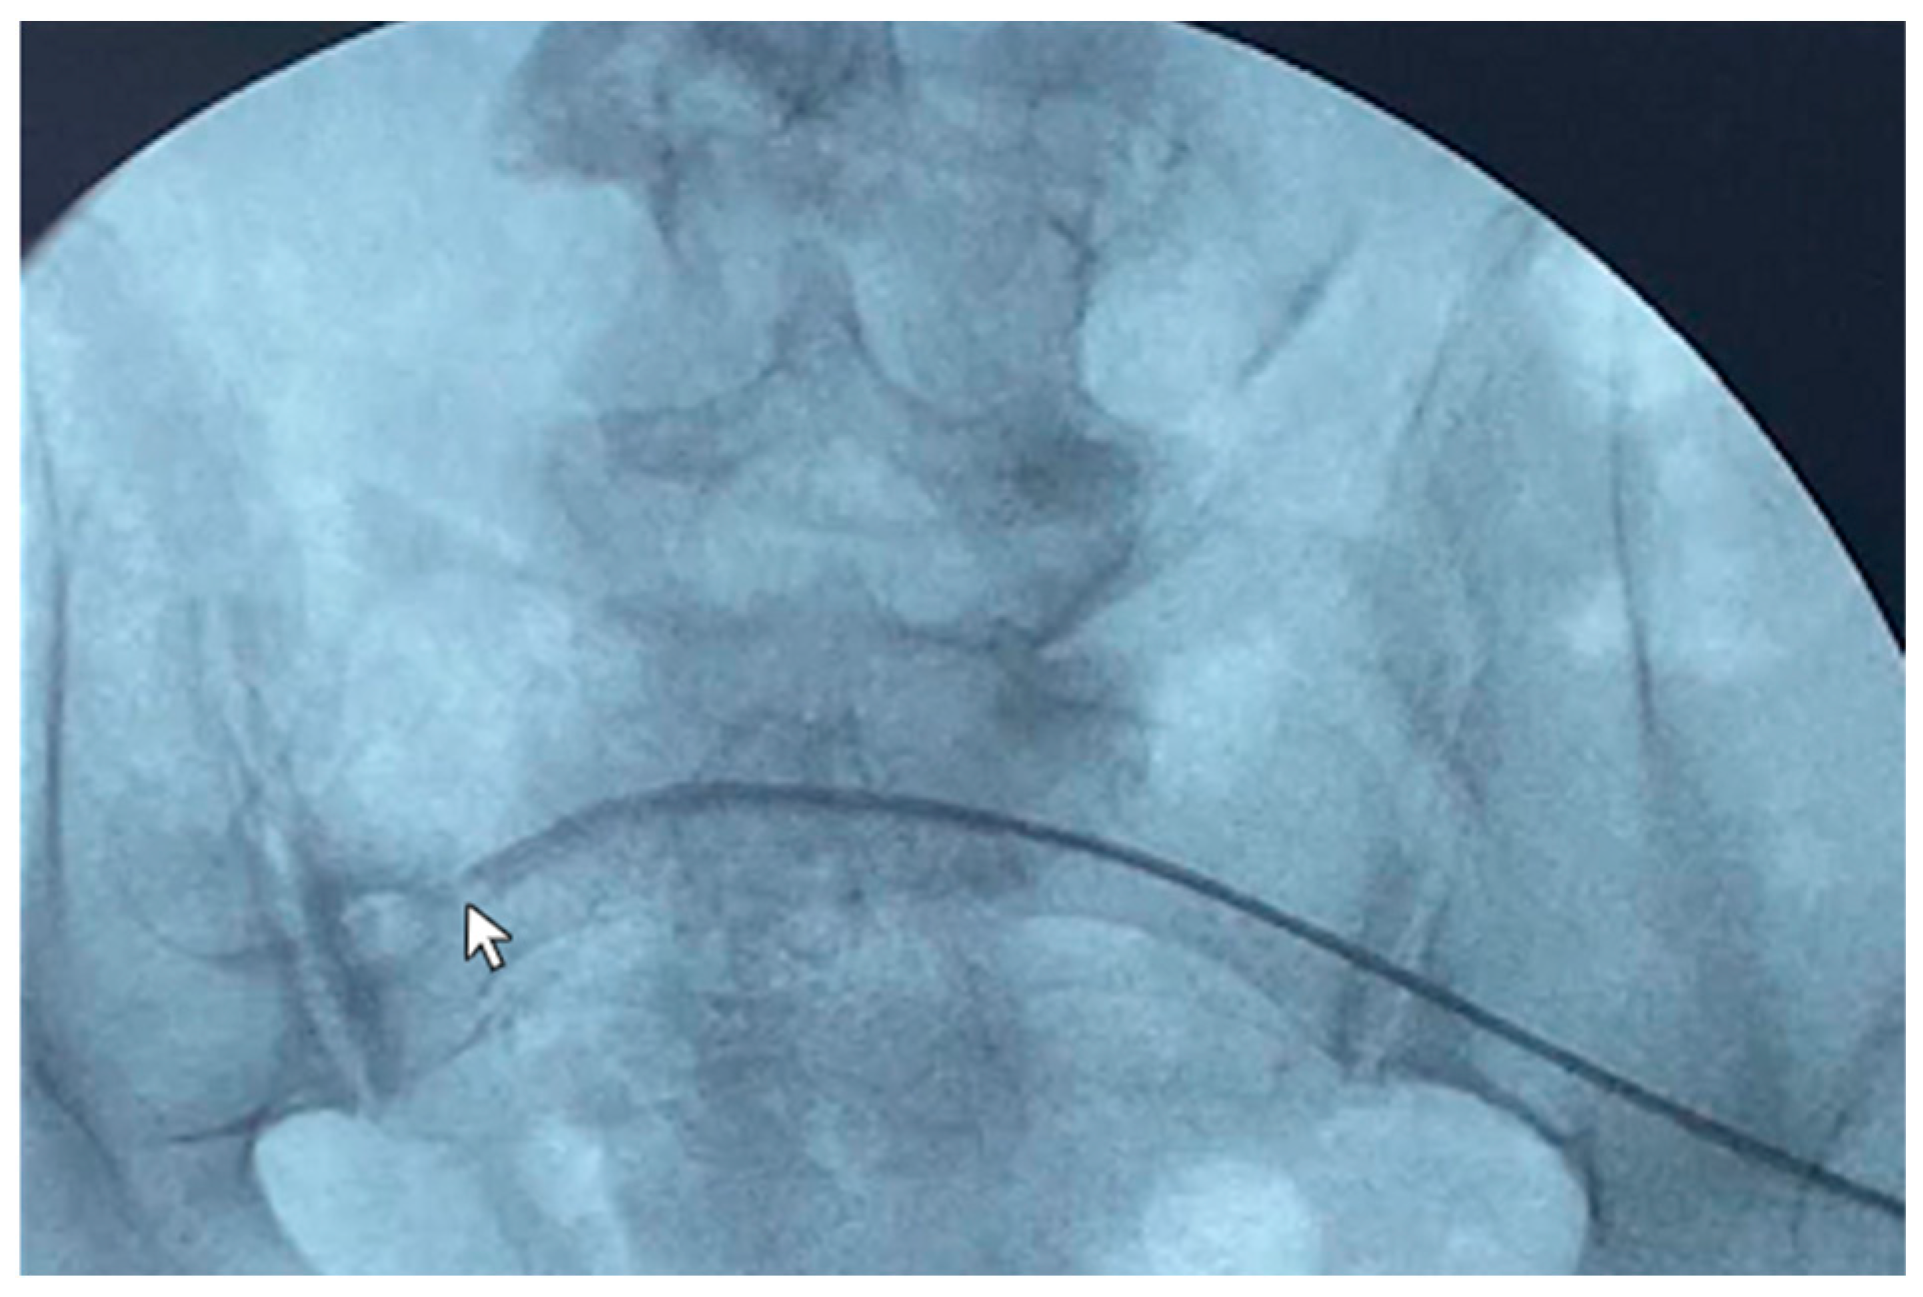

A 79-year-old female patient in peritoneal dialysis for 14 months for diabetic kidney disease was diagnosed with malfunction of the peritoneal catheter with inflow and outflow problems. The patient was thus subjected to catheterography, which showed the tip ending stuck against the right lumbar region (Figure 4). The guidewire manipulation did not manage to reposition the catheter in the pelvis, as the catheter was probably blocked by consolidated adhesions anchoring it to the abdominal side wall. No complication was reported. The patient dropped out of peritoneal dialysis and switched to hemodialysis by choice.

Figure 4. Use of the guide (Wire M—stiff type angled) to reposition the catheter tip (Life 14 01475 i002)—pointing against the right lumbar region—under radioscopic guidance.